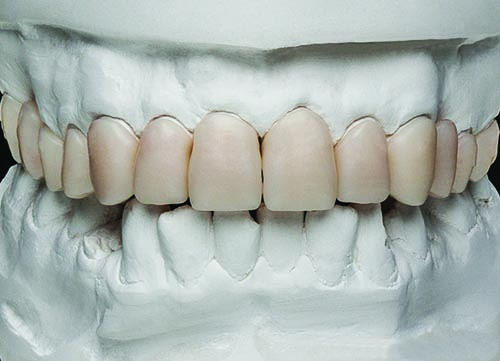

Fig. 28: The completed Telio CAD provisional restorations were tried back onto the model to verify fit and aesthetic qualities.

Fig. 29: View of the long-term provisional restorations after insertion at the second appointment. The third appointment was scheduled for four months later, during which time final preparation and refinement of teeth #2 through #14 was performed and final impressions were taken.